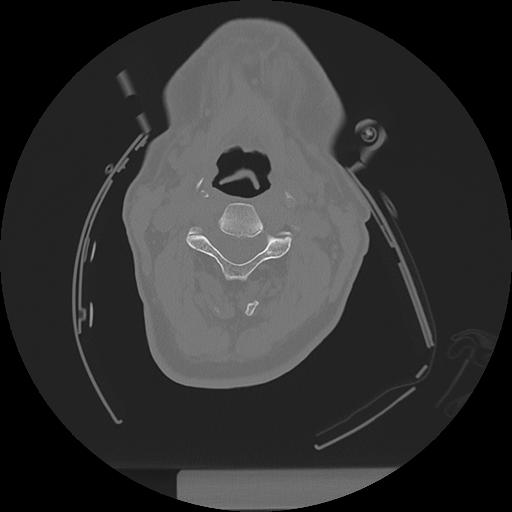

11 HUESO,,Axial,2.0,HUESO,,